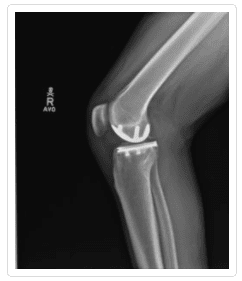

If nonsurgical treatments are not enough, you will need to have surgery. As with nonsurgical options, the purpose of surgery is to reduce pain, increase function, and generally, reduce your symptoms. Patient satisfaction is a fundamental goal in treating arthritis of the knee. There are a number of options available, including cartilage grafting, arthroscopic surgery, total or partial knee arthroplasty, and osteotomy.

Knee Arthritis Gallery

To see more examples of knees with arthritis, please visit our knee x-ray gallery.